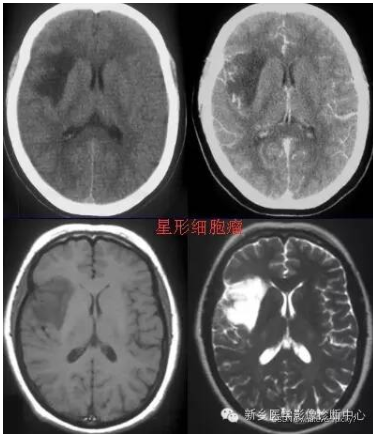

高级别(间变性星形细胞瘤和多形性胶质母细胞瘤)胶质瘤 (HGG) 和 低级别胶质瘤 (LGG) MRI(组织学诊断:星形细胞瘤或少突星形细胞瘤)组成。

本文介绍了脑部MRI图像在胶质瘤级别分类中的作用,包括高级别和低级别胶质瘤的特点,以及它们的治疗和预后。胶质瘤的病理级别直接影响治疗方案和预后,而现代影像学技术能够帮助医生在术前准确评估肿瘤的恶性程度。手术是主要治疗手段,结合放疗和化疗可提高疗效。